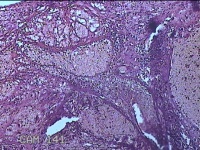

子宫腔内组织

性别

女

年龄

39岁

临床诊断

早期人工流产

一般病史

停经36天。

标本名称

大体所见

灰白暗红色不规则碎组织3x2.5x1.3cm一堆,未发现明显的绒毛样组织。

不具诊断价值。

在切片质量方面还需要加把劲。